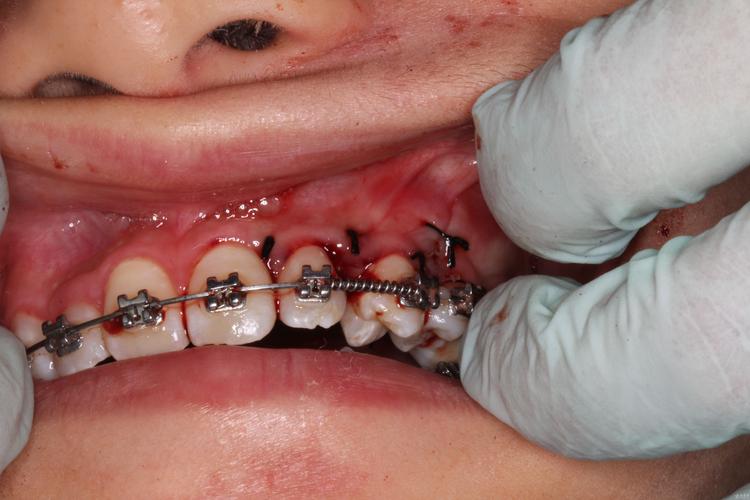

拔尖牙并非常规操作,仅适用于特定病例,需通过模型分析、X线片(全景片、头颅侧位片)等检查综合判断,以下是常见的拔尖牙适应症,可通过表格更直观理解:

以最常见的“上颌尖牙拔除”为例:拔牙后,医生会利用邻牙(如侧切牙、第一前磨牙)作为支抗,通过施加持续、轻柔的力(如镍钛丝、橡皮筋),引导前牙(切牙、侧切牙)向舌侧移动,同时后牙(前磨牙、磨牙)向近中移动,尖牙原本的位置将由侧切牙和第一前磨牙共同占据,而侧切牙会通过形态调整(如牙体预备、正畸磨改)替代尖牙的功能。

值得注意的是,牙齿移动速度并非越快越好,通常情况下,关闭一个拔牙间隙需要6-12个月,过快的移动可能导致牙根吸收、牙龈萎缩等风险,医生会定期通过X线片监控牙齿移动情况,确保牙根平行、牙槽骨健康。